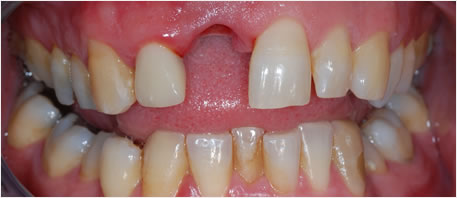

Before Dental Implant

dental implants northern ireland

After Dental Implant